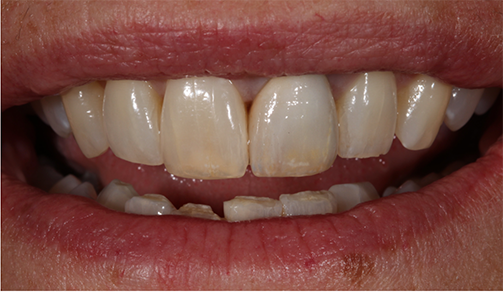

The patient also reported that she was never happy with the restoration, and she also was unhappy with the incisal chipping on tooth #8. Since she was about to embark on a new career, she wanted a smile she felt confident about.

A multitude of treatment options were discussed, including tooth whitening and placing a conservative veneer on tooth #8. The patient opted for the most minimally invasive approach, which included placing direct composite bonding on the incisal edge of tooth #8 and a new full-coverage crown restoration on tooth #9.

The comprehensive oral examination, which included radiographs, revealed nothing that would contraindicate this treatment plan (Fig. 2). In fact, the previous endodontic treatment was acceptable, and the post was well-adapted to the tooth. The risks and benefits of removing the post were discussed with an endodontist and ultimately the patient, and it was decided to leave the existing cast post and core in place. However, doing so would create prosthetic challenges, including identifying a material that offered an esthetic outcome while blocking out the dark-colored post and core. For this reason, a full-coverage crown fabricated from zirconia was recommended and accepted by the patient.